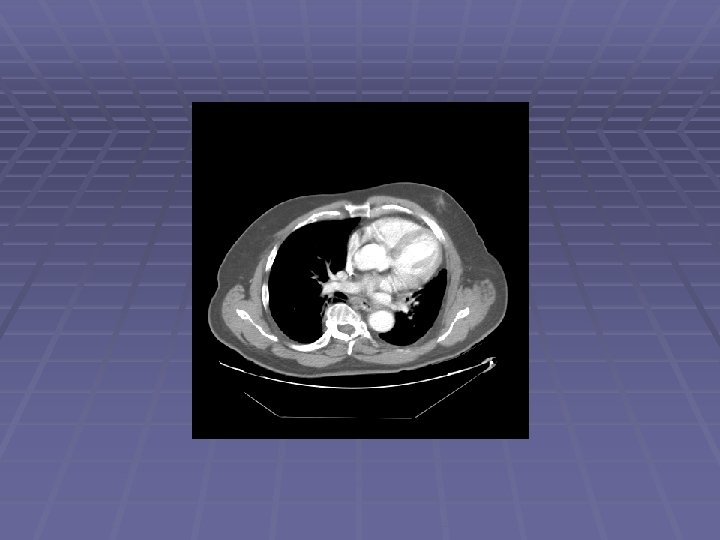

Pancreatic Mass at CT